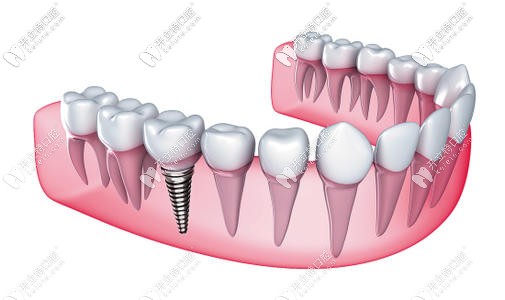

本期主要探討利用先鋒鉆導(dǎo)板輔助定位,在優(yōu)先的自體骨條件下植入種植體并即刻負(fù)重,恢復(fù)顧客牙列缺失功能及美觀的臨床效果。